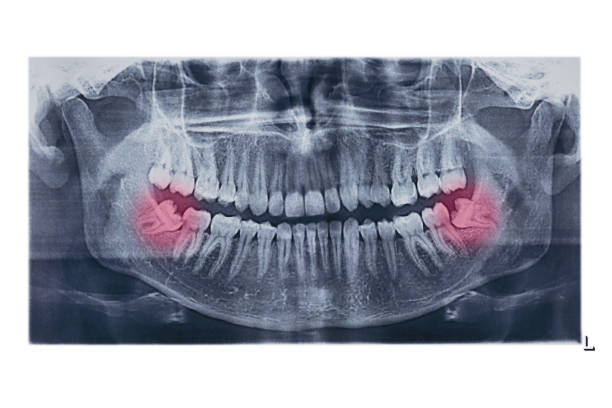

យើងមិនអាចការពារការដុះថ្គាមទាល់បានទេ។ ទោះយ៉ាងណា ទន្តបណ្ឌិតអាចតាមដានការលូតលាស់ និងការកើតនៃថ្គាមទាល់របស់អ្នក ក្នុងអំឡុងពេលពិនិត្យមាត់ធ្មេញជាប្រចាំរបស់អ្នក។ កាំរស្មីអ៊ិចធ្មេញគឺមានសមត្ថភាពអាចបង្ហាញពីការដុះថ្គាមទាល់ មុនពេលមានរោគសញ្ញា។